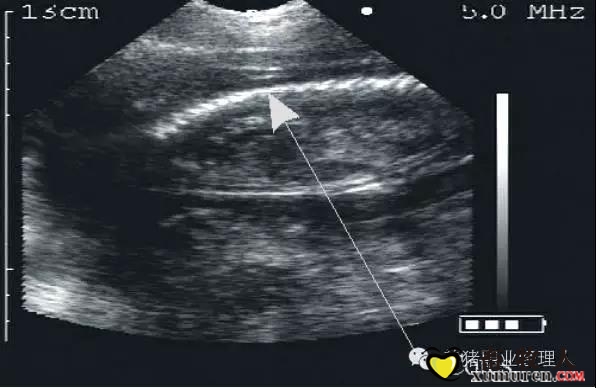

3.jpg

21天检测怀孕图